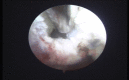

Methods: Eighteen subsequent cases of acute septic arthritis of hip and knee were included in this study. Complete hemogram, erythrocyte sedimentation rate (ESR), C-reactive protein (CRP), blood sugar, liver and kidney function test was done. Plain radiographs and ultrasound of affected joints were done. Joint aspirate was analyzed for gram staining, AFB staining, culture/sensitivity, biochemistry and cytology. Quantitative CRP was repeated every third day till normal CRP level was noted. Intravenous cloxacillin 25-50 mg/kg was started according to WHO protocol and was later changed to specific antibiotics after culture reports. Arthroscopic drainage and debridement of joints was done through standard portals and two tubes were placed in each joint for continuous suction and irrigation. Continuous suction irrigation was used till the effluent saline from the joint was clear. Functional outcome was documented as per Harris hip score for hips and Lysholm score for knee joint. Scoring was done before surgery, at one month and at three months. The duration of intravenous antibiotics and hospitalization was recorded.

Results: Out of eighteen cases 83.33% were males and 14.67% females. The mean age was 22 years (±12.01). The mean duration of symptoms was 4.33 days (±1.41). According to Gachter classification 88.88% of cases were stage 2 infection and 11.12% cases in stage 1 at the time of arthroscopy. The mean duration of hospital stay was 14.61 days (±4.01). Intravenous antibiotics were given for a mean period of 9.33 days (±2.16). The mean pre-operative Harris score was 13.6 (±2.07) which improved to 98 (±1.87) at 3 months and all the cases had painless normal range of movements. Mean pre-operative Lysholm score was 38.38 (±4.29) and it improved to 98.84 (±2.19) at 3 months. There were no sequelae of septic arthritis in any case.